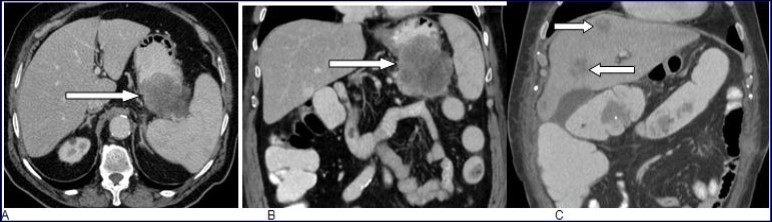

Abdominal CT scan with intravenous contrast material enhancement showed a huge mass of the gastric body, largely necrotic, infiltrating the pancreatic tail, the spleen and the left transverse colon. CT scan did not reveal any other lesion than the except gastric tumor (Figure 1. A, B).

Figure 1.A and B, Abdominal CT scan with intravenous contrast enhancement showed a huge mass of the gastric body, largely necrotic, infiltrating the pancreatic tail, the spleen and the left transverse colon. CT scan did not reveal any other lesion except the gastric tumor. C: Multiples liver metastases two months after surgical operation.

Follow-up thoracic-abdominal CT scan obtained two months after surgical operation showed liver and lung metastasis and multiple retroperitoneal lymph nodes (Figure 1, C). Palliative chemotherapy was then indicated. Unfortunately, the patient's condition deteriorated rapidly and he expired three months later.